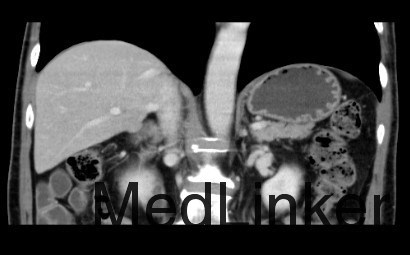

查体: 左上腹外侧见手术切除,余无异常。 辅助检查: 1、检验 白细胞WBC 6.15x10^9/L,血红蛋白Hb 165 g/L,血小板PLT 173x10^9/L;乙肝表面抗原HBsAg(-),乙肝核心抗体HBcAb(+);AFP, CEA、CA125、CA19-9均正常范围 2、影像学 CT:肝S6内缘包膜下结节(19×17mm、19×19mm,),考虑肝细胞癌可能性大,建议进一步检查;其相邻低密度结节,不除外肝囊肿。 2.右侧肾上腺结节,考虑转移瘤可能性大。 3.双肾囊肿。

临床诊断 肝细胞癌 治疗: 手术切除右侧肾上腺转移瘤和右肝肿瘤 术后病理: 1、(肝)送检4x3x2cm灰褐色组织一块,切面灰黄,质软。 镜下:送检肝组织内见境界较清楚的胶原纤维包裹的坏死结节,其内可见肿瘤残影,建议结合临床患者是否行介入等治疗,则可符合治疗后改变,未见残留肿瘤细胞。另一组织提示增生的肝细胞Glypican-3灶性(+),CD34显示增生的结节毛细血管化。 特殊染色:网状纤维染色显示肝细胞索增生。 结合HE形态及免疫组化结果,病变符合肝细胞癌。 2(肾上腺结节)送检5x3x3cm淡黄组织一块,可见直径2cm灰白结节。 镜下:肾上腺组织内见肝细胞癌浸润。

心得体会 肝细胞癌最容易发生转移的部位为肝内,其次为肺、骨,再者可能就为肾上腺,该病例第一次治疗由于左侧肾上腺肿物而起,而术后病理提示肝细胞癌才发现了肝内病灶和右侧肾上腺肿物,这种情况相对少见。